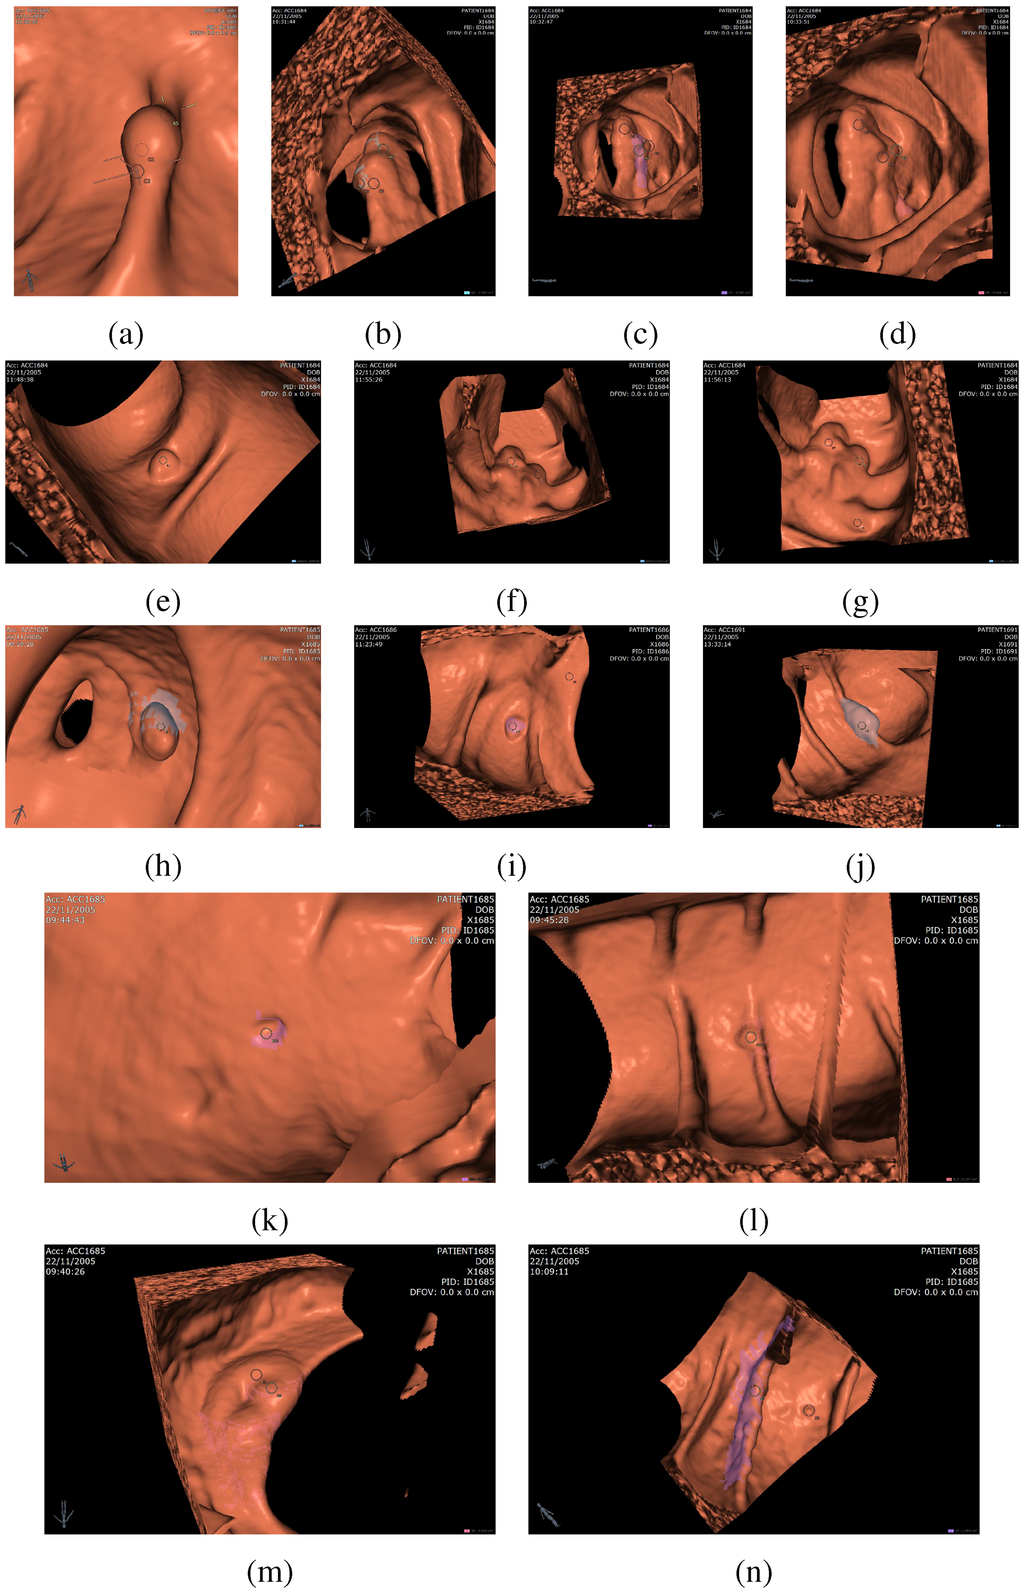

Figure 9. Examples of detected polyps and false positives, (a)-(l) are examples of detected polyps, (m)-(n) are examples of false positives. In particular, successfully detected sessile polyps appear in (e), (i), and (k), pedunculated polyps in (d) and (h), and polyps on folds in (a), (j), and (l). False positives shown in the figure relate to the ileocecal valve (m) and a thick fold (n).

Figure 9 gives visual examples of detected polyps (a)-(l) and false positives (m)-(n). The CAD system accurately detects sessile polyps (e.g., (e), (i), (k)) as well as pedunculated polyps ((d), (h)) and polyps on haustral folds ((a), (j), (l)). One common source of false positives is the ileocecal valve (ICV), which is the valve that connects the colon to the small bowel. The ICV often appears as a protruding shape in the colonic lumen and is picked up by the CAD as a false positive, shown in (m). A false positive appearing on a thick haustral fold is shown in (n). Some true positive diminutive polyps (less than 6 mm) may be detected by the CAD, as shown in (k)-(l). These polyps cannot be avoided entirely since the match between the detected region diameter and the actual lesion diameter is not exact in all cases.